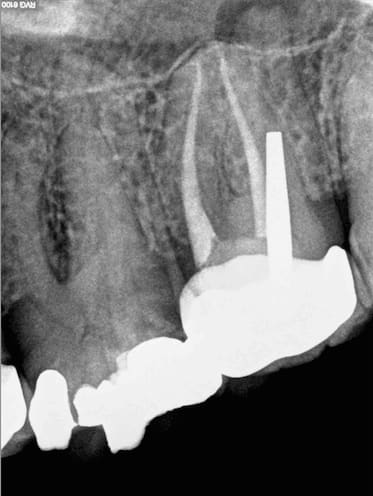

chicot29

29/02/2016 à 16h55

Pas mal. Celle d'hokusai est plus réaliste. Tu peux faire mieux. Il faut s'appliquer pour les RTE. -)

Dis moi un CDC n'a pas le droit de faire de radio administrative pour vérifier non ? -)

barbabapat

29/02/2016 à 17h25

Je voulais pas allumer l'ordi, donc, travail juste à la tablette avec les logiciels gratuit sous android en moins de 30 minutes.

Après, j'aurai dû mieux utiliser les outils de transparences des calques avant de les fusionner.

Enfin, plutôt que défiscaliser photoshop, ça permet d'expliquer au contrôleur des impôts pourquoi tu défiscalise ton smartphone.